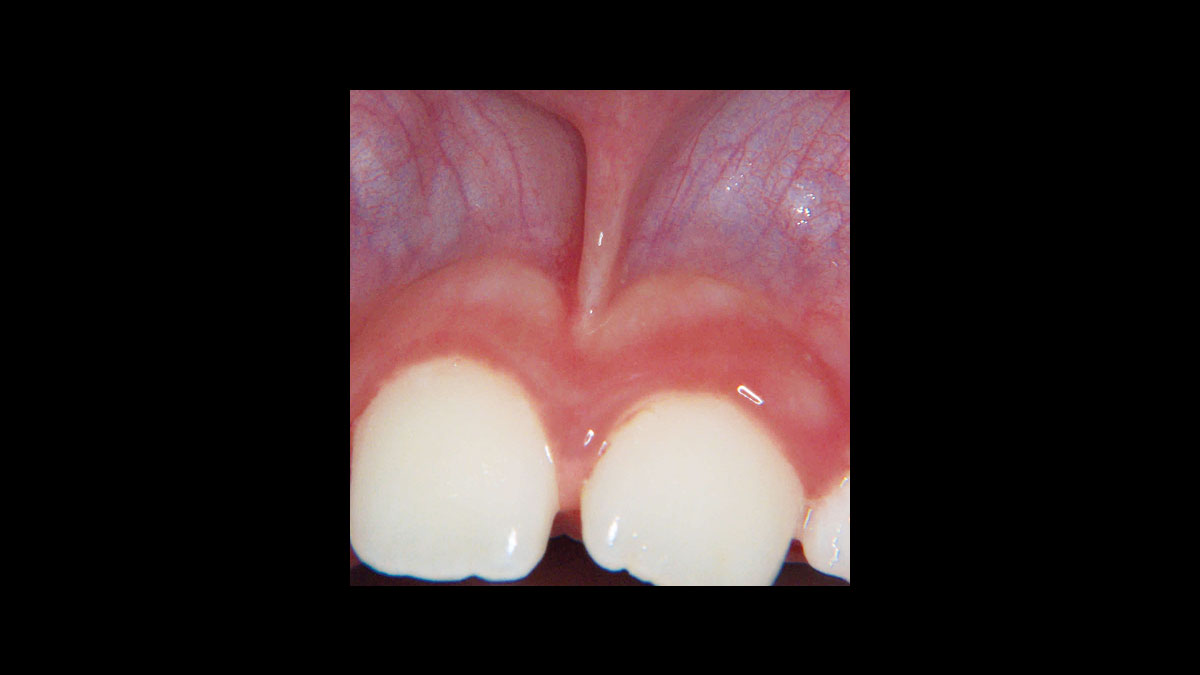

• Frenectomy

Frenectomy